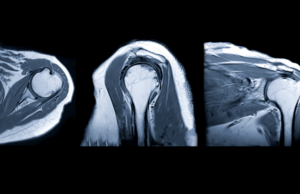

Resonancia magnética abierta de hombro

La resonancia magnética (RM) es una herramienta clave en el diagnóstico médico moderno, especialmente cuando se trata de evaluar problemas en áreas complejas y delicadas como el hombro. La resonancia magnética abierta de hombro ofrece una opción menos claustrofóbica y más cómoda para los pacientes, mientras proporciona imágenes detalladas y precisas. Así que vamos a … Sigue leyendo Resonancia magnética abierta de hombro